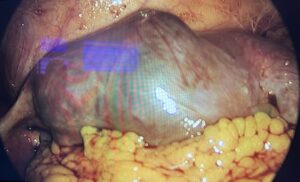

The patient was diagnosed with a unilateral tubal twin pregnancy. The findings and available therapeutic options were discussed, and laparoscopic surgical management was selected. The procedure was performed using a 12-mm umbilical trocar and two 5-mm accessory trocars placed in the left iliac region. Intraoperatively, a right adnexal mass was identified, corresponding to a tubal lesion measuring approximately 84 × 45 mm (Figure 2). After careful inspection of the entire abdominal cavity, a right salpingectomy was performed (Figures 3 and 4) without complications. The surgical specimen was retrieved in a closed extraction bag through the umbilical trocar and sent for histopathological examination. The postoperative course was uneventful, and the patient was discharged 12 hours after surgery. Histopathological analysis confirmed a tubal TEP, identifying two embryos.